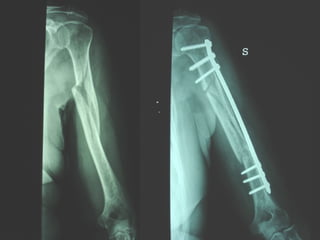

Dal Gennaio 2000 al Febbraio 2006 abbiamo trattato 167 fratture chiuse  con placca percutanea  in 164 pazienti :  27 lesioni diafisarie di gamba, 12 piloni tibiali ,  11 fratture prossimali di tibia, 36 fratture sovracondiloidee di femore, 17 fratture diafisarie di femore, 43 fratture metaepifisarie prossimali di omero, 21 diafisarie d’omero.  156 guarigioni 8 fallimenti

Dal Gennaio 2000 al Dicembre 2005 27 placche LISS di femore